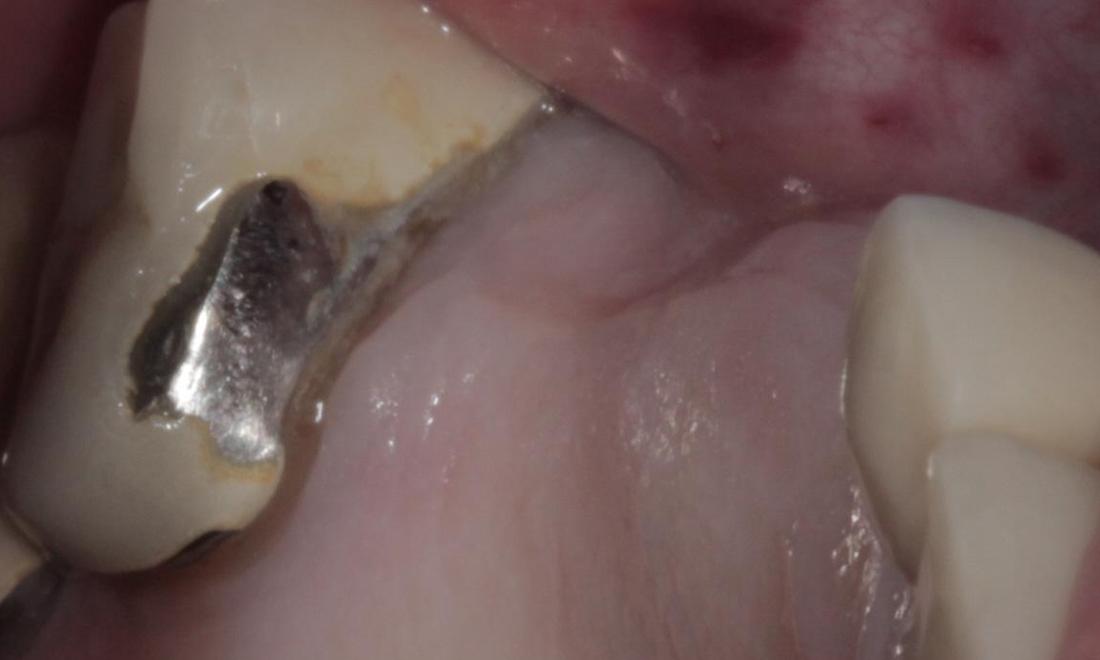

Mini Implant Bridge

This patient had been wearing a removable partial denture for years and was not happy with it. He complained of it moving while he chewed, and said he could not eat many of the foods that he enjoyed. After careful planning, 5 mini dental implants were placed, and a custom bridge was cemented into place. He is now able to chew food again on that side, and he does not have to worry about removing his teeth at night before bed. He called the day after the implants were placed to let us know he was on his way out to go fishing!